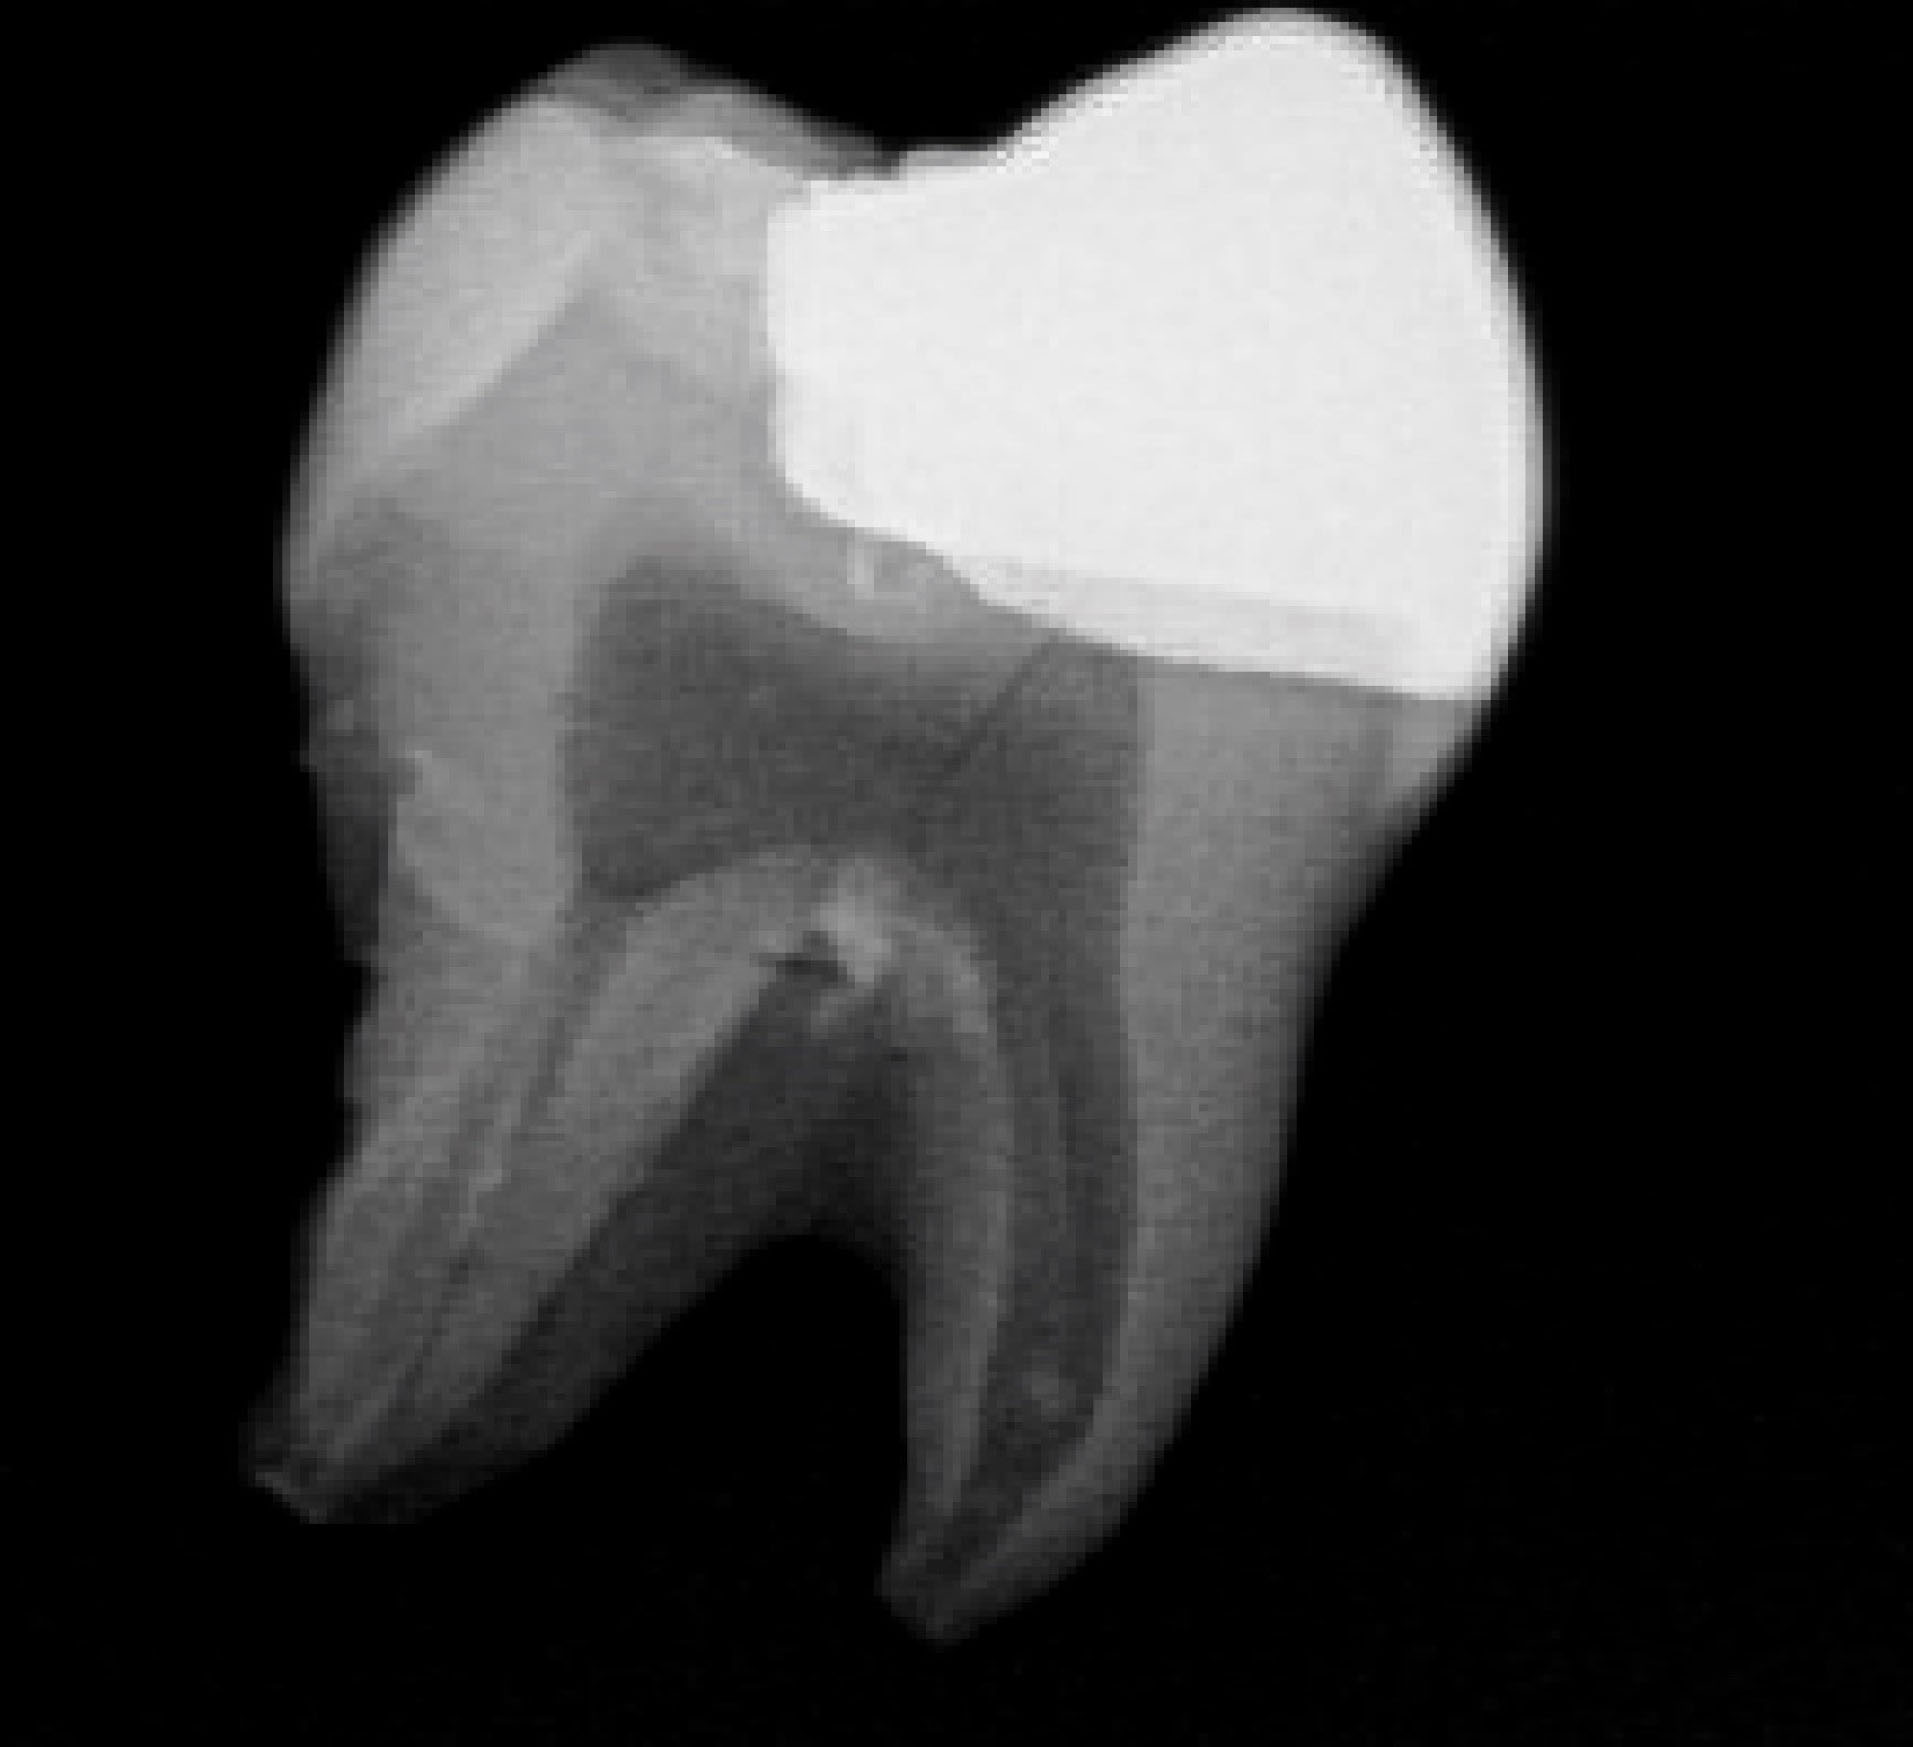

Each onlay was bonded to its corresponding prepared tooth using resin cement (GC, Alsip, United States) following the manufacturer’s protocol. 5 The restorations were then polished with high-speed diamond burs and slow-speed finishing discs. Post-cementation photographs were taken of the restorations in buccal, lingual, mesial, distal and occlusal views ( and ). Radiographs were also taken for each restoration in mesiodistal and buccolingual aspects ( and ).

joddd-15-147-g009

Figure 9. Mesial-distal radiographic view of the cemented onlay.

joddd-15-147-g010

Figure 10. Buccal-lingual radiographic view of the cemented onlay.

The digital scanner provided an STL file of suitable resolution for three-dimensional (3D) printing in metal. The indirect onlay restorations were successfully 3D-printed in cobalt-chromium with dimensions, morphology, and fit clinically acceptable for subsequent cementation. Cementation was unremarkable and adequately retained the onlays, similar to previous investigations. 6 Marginal adaption was generally acceptable but was clinically unacceptable in one area due to an open margin. The surface finish was generally acceptable but could be improved in some areas, especially on the occlusal surface.